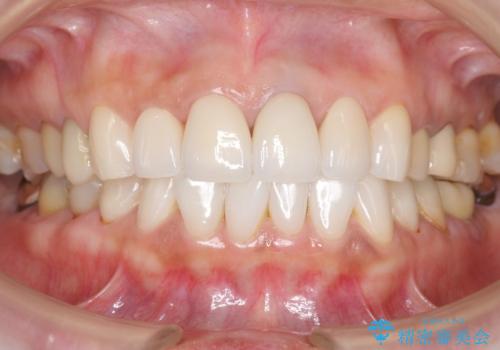

5年前に行った治療に大変ご満足頂き、他の部位も治療やホワイトニングを希望して下さいました。

人工のダイヤモンドにも用いられるジルコニアは、セラミック系素材の中でも圧倒的に丈夫かつ審美的で、劣化しにくく口腔内でも長期間安定した状態を保つことができます。

クラウンの種類:ジルコニアオールセラミッククラウン スタンダード